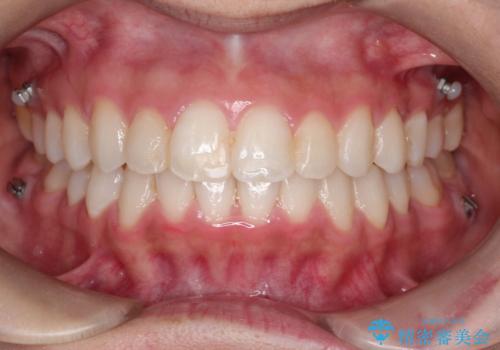

患者様にしっかりとインビザラインを使用して頂けたことで綺麗な仕上がりとなりました。

- 上下の歯の凸凹を主訴に来院されました。

当院での検査にて非抜歯+インビザライン矯正を提案させていただき治療を行なっております。